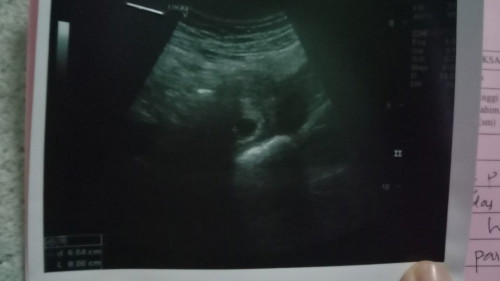

Hai sape2 ibu ada mcm saya keluar darah sikit tapi xsakit tapi cek ape semua kantung masih ada cume baby belum nampak sbb masih kecil...

Saya pon start spotting coklat dari 5W pregnancy dalam 2-3 hari, mmg tak sakit doc kasi duphaston to support pregnancy.. 7W last time nampak kantung and yolk sac shj. Still continue makan duphaston 2x sehari till now. Alhamdulillah pergi check up selepas 8W baru nampak baby and dengar heartbeat. Tunggu je sis, bykkan berdoa.

hari ini sy cek dokto masih xnampak kantung terpakse temujanji 2 minggu nanti...